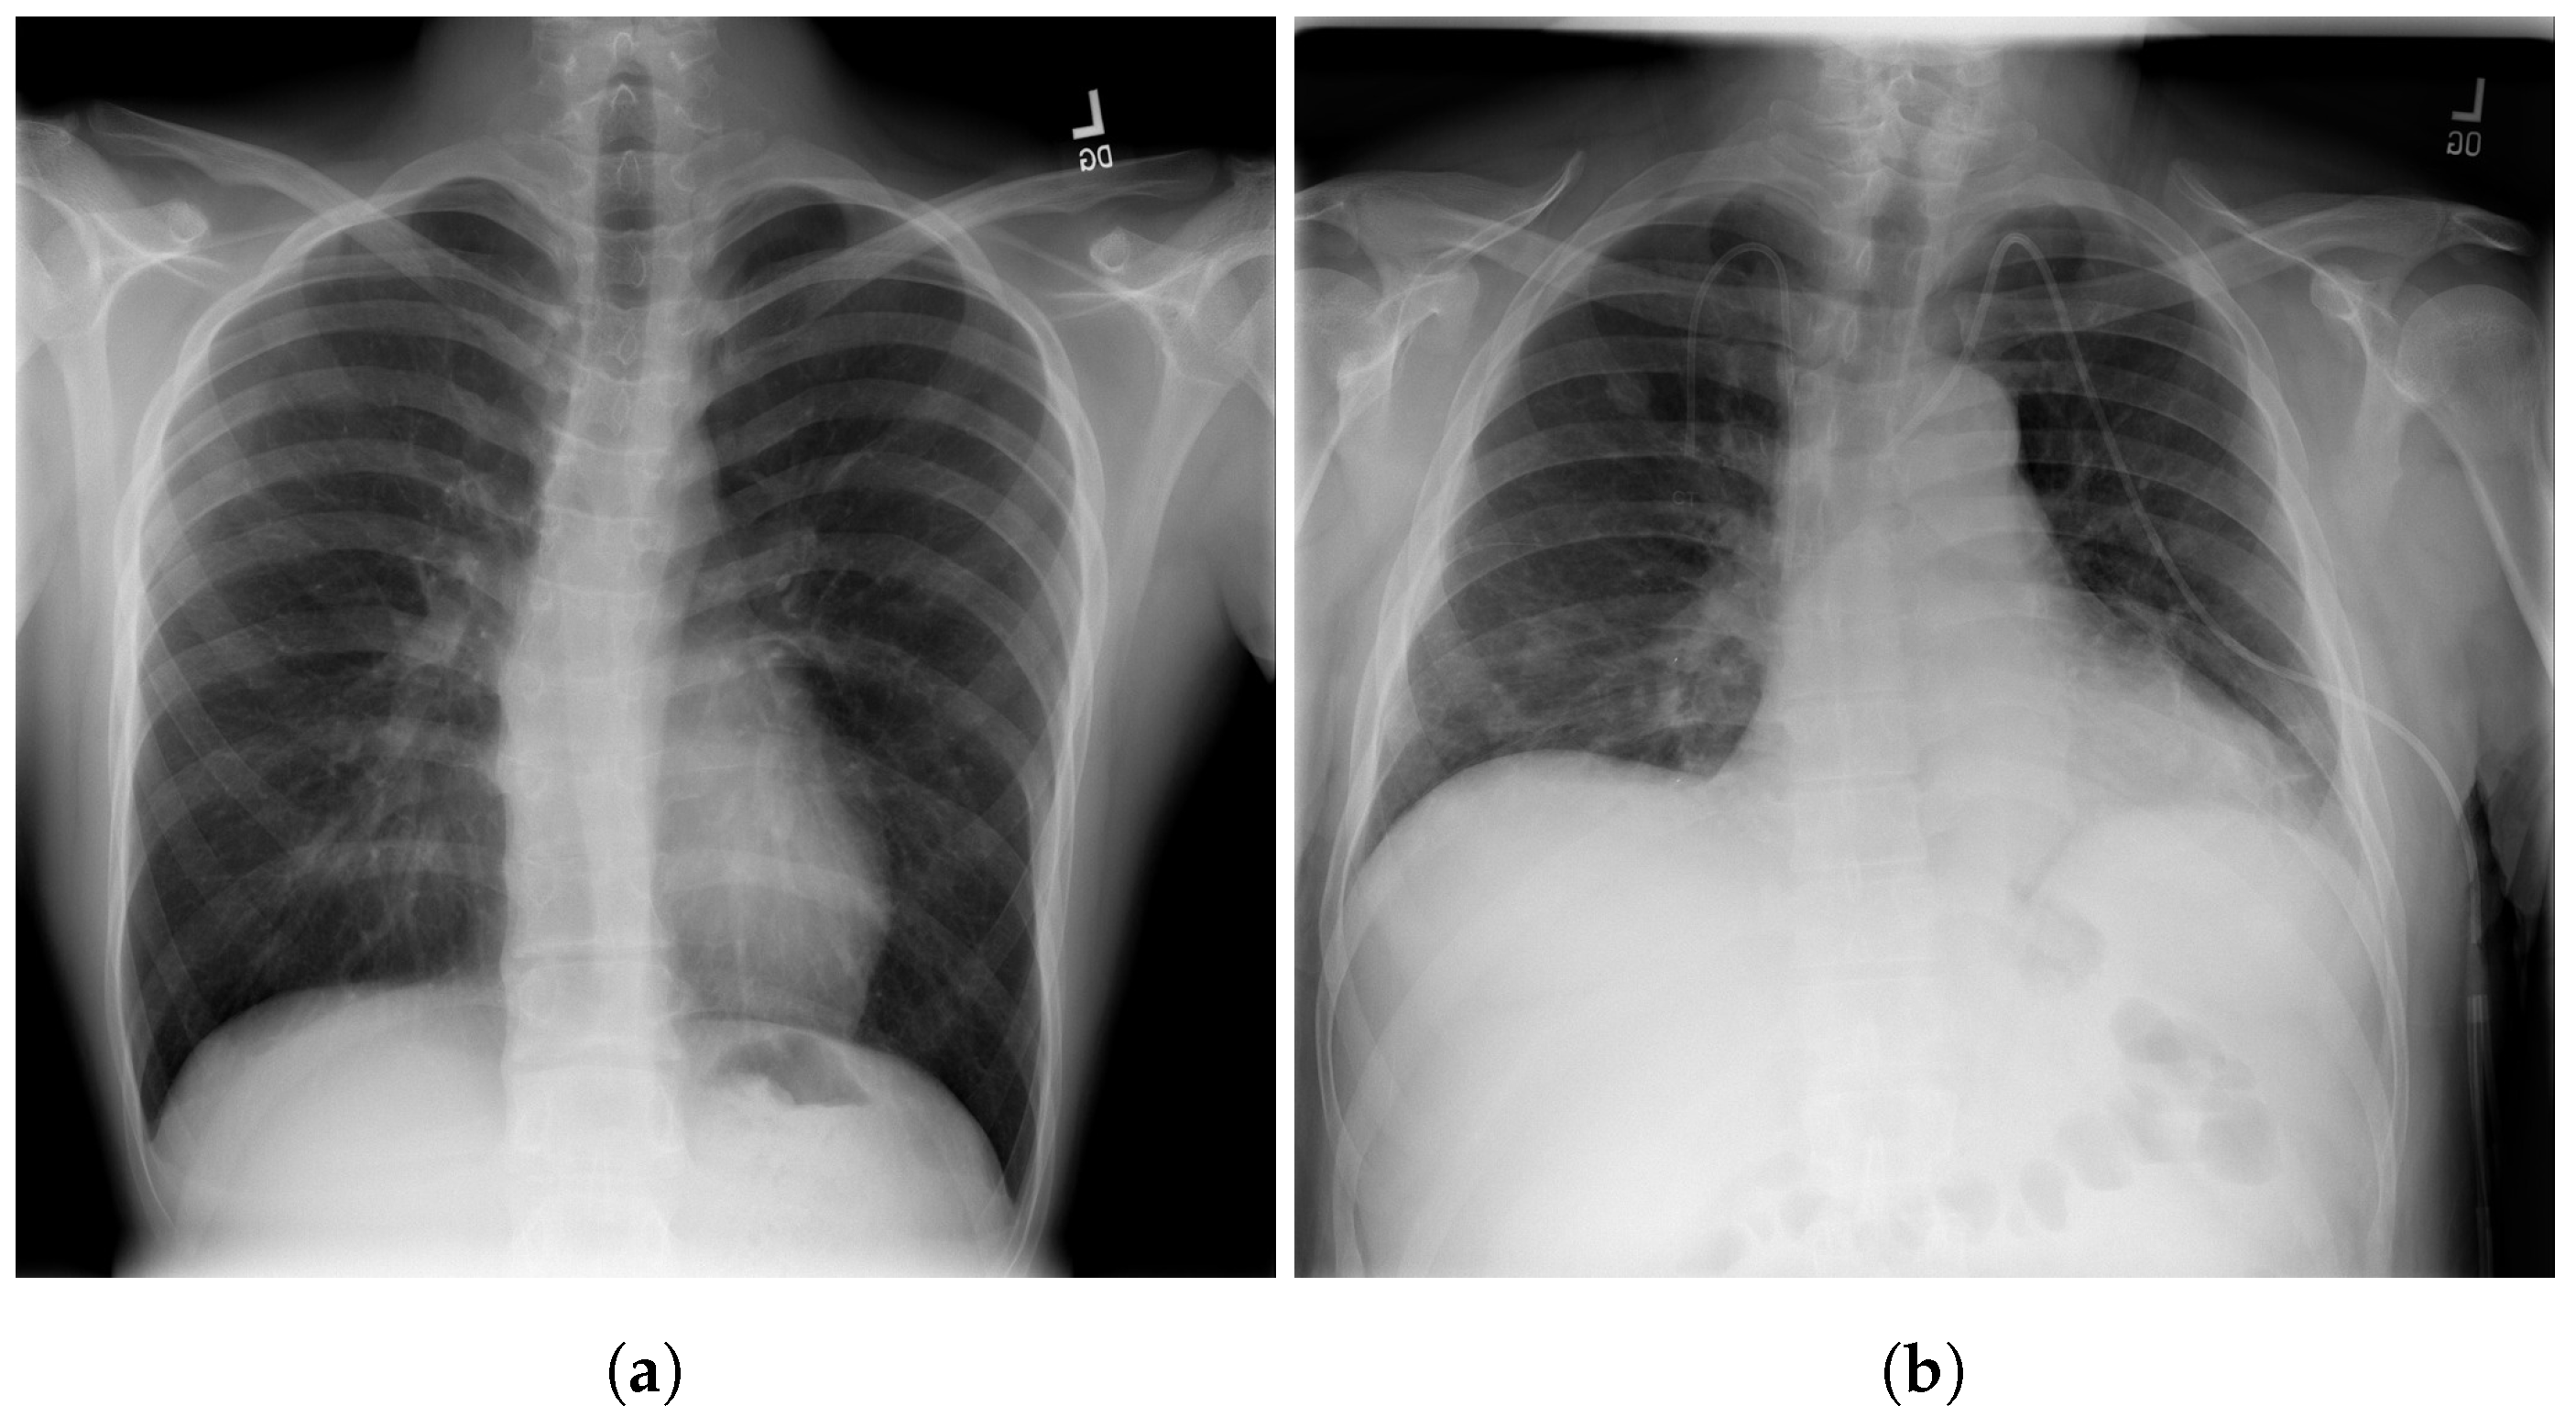

The RSNA dataset [3] is a public dataset of CXR images with patients’ metadata. This dataset was provided for a challenge in Kaggle by the US National Institutes of Health Clinical Center [33]. It contains 26,684 CXR images for unique patients, and each image is labeled with one of three different classes from the associated radiology reports: ’Normal’, ’No Lung Opacity/Not Normal’, and ’Lung Opacity’. Figure 3 shows images examples from the RSNA dataset.

Figure 3.

Examples of RSNA images: (a) Normal; (b) Pneumonia [3].